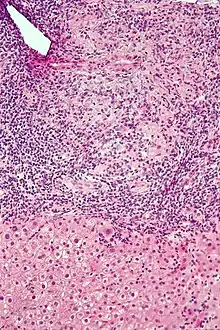

Low-magnification micrograph of PBC, H&E stain

Low-magnification micrograph of PBC, H&E stain Intermediate-magnification micrograph of PBC showing bile duct inflammation and periductal granulomas, liver biopsy, H&E stain

On microscopic examination of liver biopsy specimens, PBC is characterized by chronic, nonsuppurative inflammation, which surrounds and destroys interlobular and septal bile ducts. These histopathologic findings in primary biliary cholangitis include:[32]

- Inflammation of the bile ducts, characterized by intraepithelial lymphocytes

- Periductal epithelioid granulomas.

- Proliferation of bile ductules

- Fibrosis (scarring)

The Ludwig and Scheuer scoring systems have historically been used to stratify four stages of PBC, with stage 4 indicating the presence of cirrhosis. In the new system of Nakanuma, the stage of disease is based on fibrosis, bile duct loss, and features of cholestasis, i.e. deposition of orcein-positive granules, whereas the grade of necroinflammatory activity is based on cholangitis and interface hepatitis. The accumulation of orcein-positive granules occurs evenly across the PBC liver, which means that staging using the Nakanuma system is more reliable regarding sampling variability.